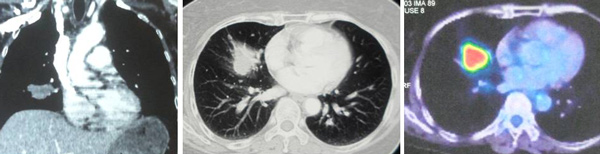

MRI thoraco-lumbar spine done in Hospital C, 3 October 2017.

- abnormal signal intensity within C7,T1 and T2 vetebral bodies. Features suggestive of metastases.

- L4/L5 disc bulge.

- L5/S1 disc bulge.

Whole body PET Scan done in Hospital C, 21 August 2018.

- metabolic activity node see in the left (1.3 cm) side of the neck.

- metabolic activity left axillary lymph node (0.6 cm).

- FGD-avid mass (4 cm) seen in the apical segment of the lower lobe of left lung. This is larger and has more metabolic activity compared to the previous PET CT on 18 Jan. 2018.

- metabolic active nodule (1.9 cm) seen in the posterior segment of the upper lobe of right lung – not seen in the previous scan.

- another metabolic active nodule (1.7 cm) seen in the posterior basal segment of the lower lobe of the left lung — not seen in the previous scan.

- a few 2-5 mm, non metabolic active nodules seen in the right and left lungs. These are not seen in the previous scan.

- increased metabolic activity seen in the left adrenal gland (1.4 cm).

- metabolic active lesions seen in the spine of C7 and T1. These re larger and more metabolic active compared to the previous PET CT scan.

- metabolic active bony lesions seen in the spine T12, left sacrum and medial wall of the left acetabulum. These are not metabolic active in the previous scan.